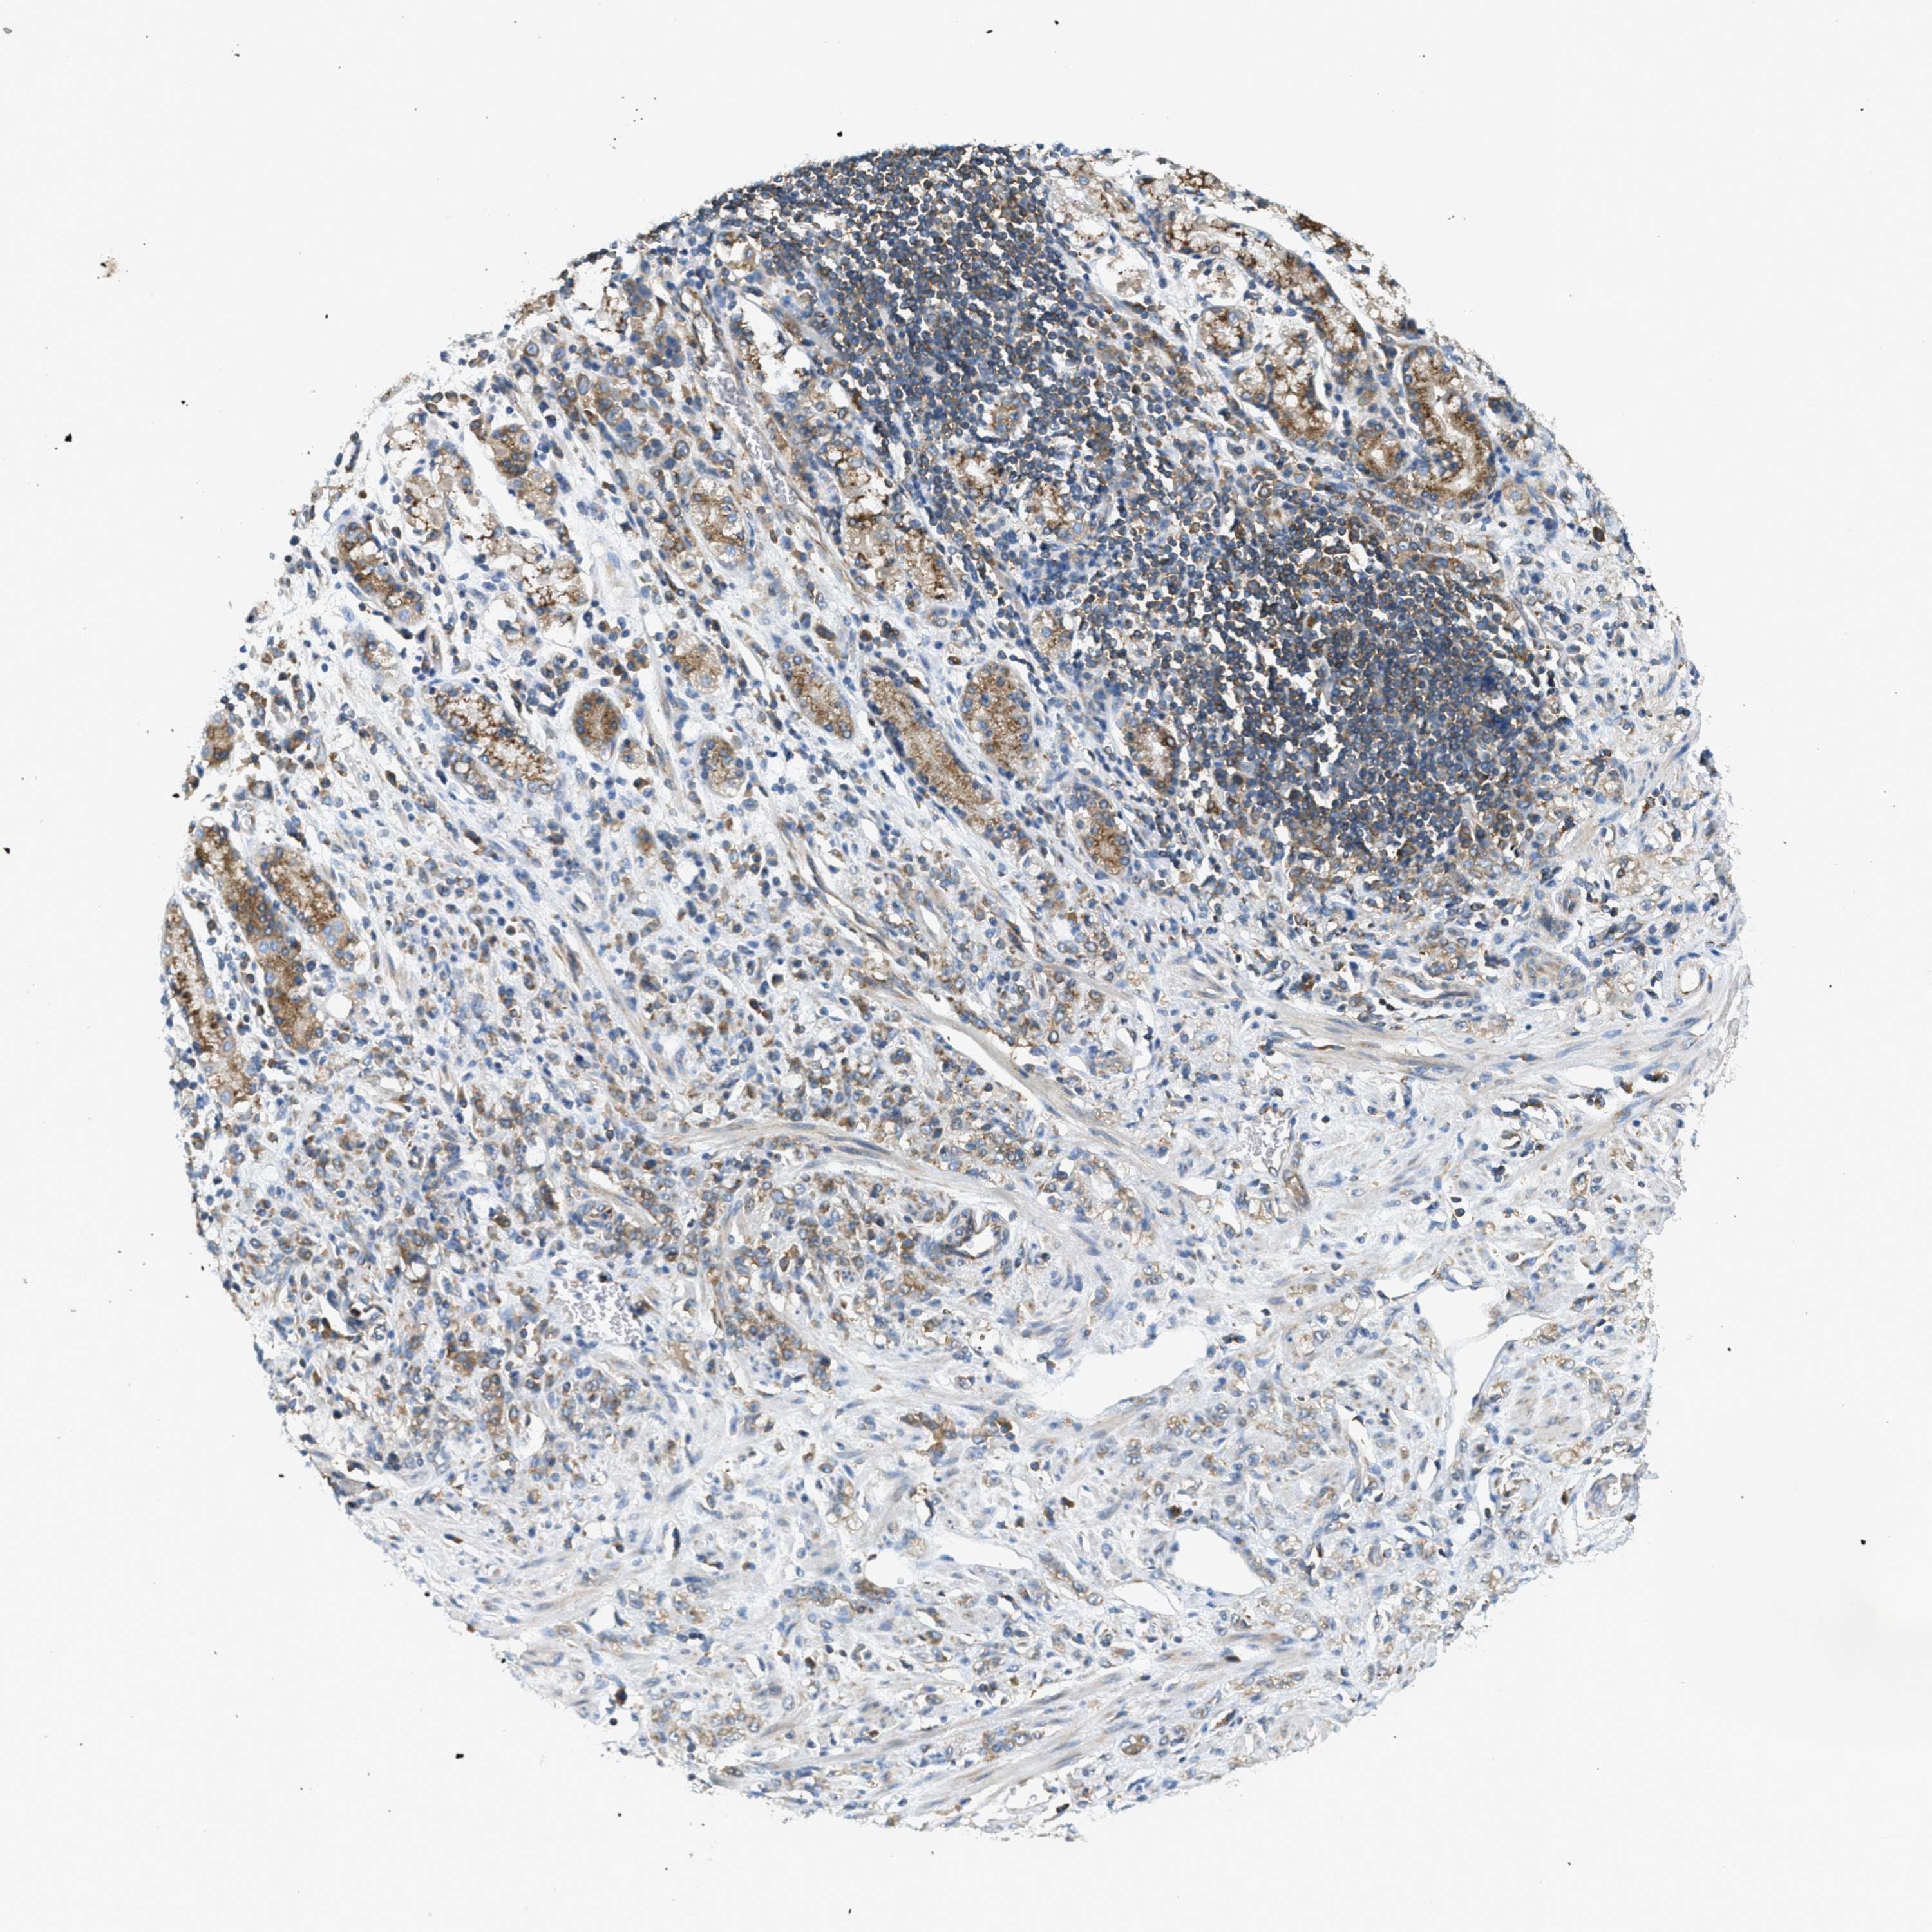

STOMACH CANCER - Protein expressioni

A mouse-over function shows sample information and annotation data. Click on an image to view it in a full screen mode. Samples can be filtered based on level of antibody staining by selecting one or several of the following categories: high, medium, low and not detected. The assay and annotation is described here.

Note that samples used for immunohistochemistry by the Human Protein Atlas do not correspond to samples in the TCGA dataset.

Antibody stainingi

Antibody staining in the annotated cell types in the current human tissue is reported as not detected, low, medium, or high, based on conventional immunohistochemistry profiling in selected tissues. This score is based on the combination of the staining intensity and fraction of stained cells.

Each image is clickable and will lead to virtual microscopy that enables deeper exploration of all samples and also displays staining intensity scores, fraction scores and subcellular localization as well as patient and tissue information for each sample.

Antibody HPA017578

Staining

High

Medium

Low

Not detected

Intensity

Strong

Moderate

Weak

Negative

Quantity

>75%

75%-25%

<25%

None

Location

Nuclear

Cytoplasmic/membranous

Cytoplasmic/membranous,nuclear

Adenocarcinoma, NOS